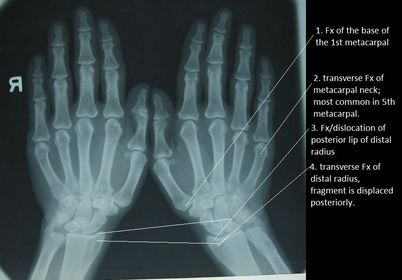

1. Bennett's Fx 2. Boxer's Fx 3. Barton's Fx 4. Colle's Fx

Smith's Fx